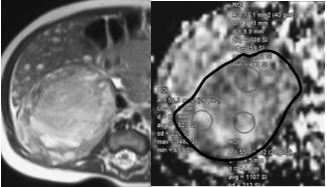

The authors of this study examined the potential use of diffusion-weighted imaging for non-invasive prediction of tumour dignity and prognosis in paediatric patients with neuroblastic tumours.

Article: Quantitative DWI predicts event-free survival in children with neuroblastic tumours: preliminary findings from a retrospective cohort study